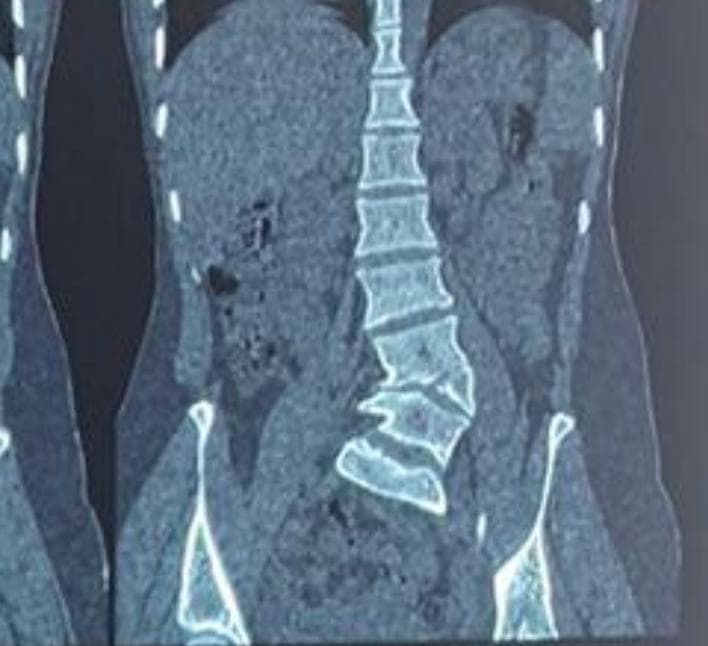

Scoliosis, an abnormal curvature of the spine, can significantly impact a person’s posture, balance, and quality of life, especially when present from birth. One such condition, congenital scoliosis, arises due to malformations in the spine during fetal development. A hemivertebra is a common cause of this, where a part of the vertebra fails to develop completely, leading to an asymmetric spinal curve that worsens over time.

This is the story of a 17-year-old girl who battled congenital scoliosis caused by a hemivertebra at the L4 level, and how timely surgical intervention helped transform her life.

A hemivertebra is a wedge-shaped vertebra that disrupts the normal alignment of the spine, often resulting in progressive scoliosis. When left untreated, especially in growing children and adolescents, the curvature tends to worsen with age, leading to severe spinal imbalance, chronic pain, restricted lung function, and psychosocial challenges.

In this patient’s case, the hemivertebra at L4 created a significant lumbosacral curve that affected the natural biomechanics of the spine, causing pain, a tilted posture, and aesthetic concerns.